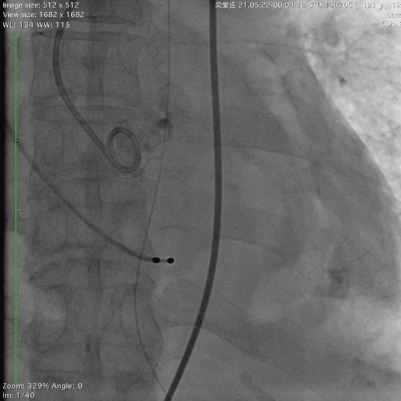

78岁的阿婆,入院3年余前出现活动后胸闷,气促。3天前出现恶心,呕吐,双下肢水肿,来广东省人民医院急诊科就诊,行心脏彩超提示为重度主动脉瓣狭窄并中度关闭不全,经郭惠明主任团队评估后收住入院,拟行TAVR治疗,阿婆急性心衰,呼吸急促,循环不稳,我院ICU团队立刻对患者进行抢救处理,紧急气管插管,循环不稳定,大剂量血管活性药物维持,尿少,乳酸持续升高,命悬一线。郭惠明刘健主任团队立刻对患者施行紧急救治,23点40麻醉,00:30开始手术,01:27分手术结束,整个手术过程持续不到1小时。